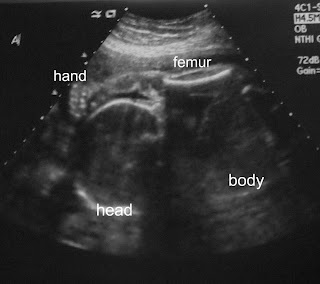

we promised one of our players we wouldn't call them Double Trouble. But the ultrasound tech missed the memo.

crazy flexible gymnast baby